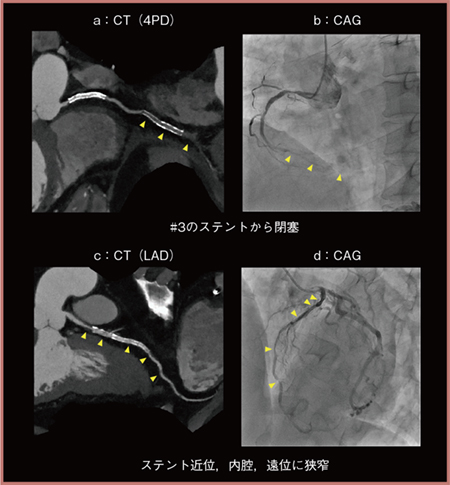

triple rule outの適応となった症例を提示する。50歳代,90kg,冠動脈形成術後の症例で,胸痛のため当センターを受診した。心筋逸脱酵素の上昇はなく(トロポニンT陰性),心電図にも異常を認めないためtriple rule out撮影を行った。volume rendering(VR)画像では肺塞栓や大動脈瘤,大動脈解離は認めなかったが(図4),冠動脈CTを見ると♯3のステントから閉塞しており(図5 a▶),末梢は側副血行路にて灌流されていた。側副血行を供給する前下行枝(LAD)には,ステントの近位部,内腔,遠位部に狭窄を認め(図5 c▶),それらによる虚血イベントであることが1回の検査で評価可能であった。冠動脈造影検査(CAG)でも同様の所見が得られた(図5 b,d▶)。

図5 Triple rule out撮影における冠動脈の評価(PIQE適用)